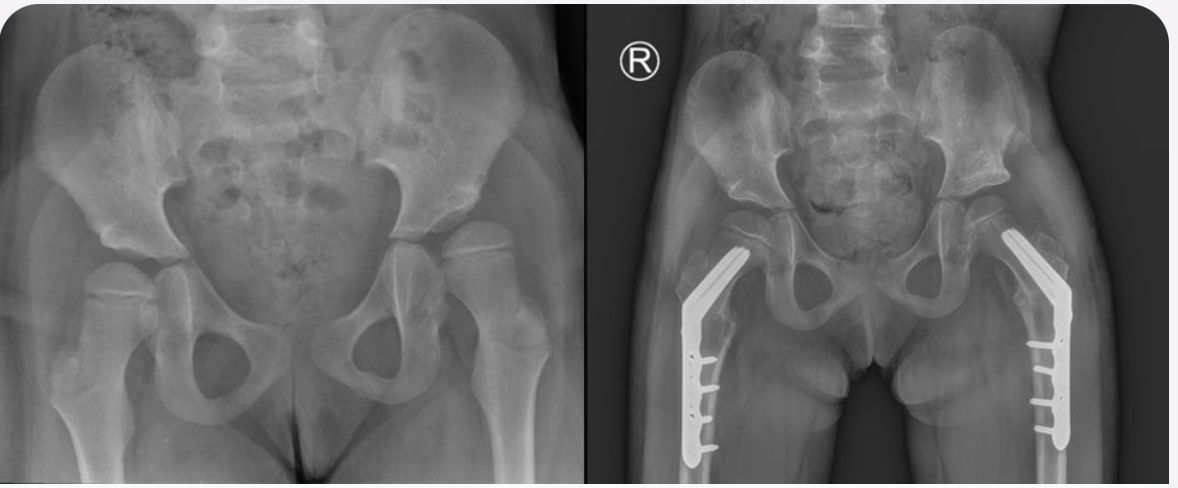

Jestem chirurgiem specjalizującym się w zaawansowanych rekonstrukcjach stawów oraz wydłużaniu kończyn dolnych (limb lengthening and reconstruction surgery). Kompleksowo opiekuję się osobami z problemami o podłożu ortopedycznym oraz neurologicznym, szczególnie dzieci z wadami wrodzonymi i schorzeniami nerwowo-mięśniowymi. Dzięki wieloletniemu doświadczeniu w nowoczesnych technikach rekonstrukcyjnych znacząco udoskonaliłem metody chirurgicznego leczenia dzieci z problemami neurologicznymi, otwierając przed nimi nowe możliwości poprawy funkcjonalności oraz jakości życia. Specjalizujemy się w jednoczasowych wielopoziomowych rekonstrukcjach kończyn (SEMLS) oraz kompleksowych rekonstrukcjach stawów biodrowych, łącząc sprawdzone techniki operacyjne z innowacyjnymi rozwiązaniami. Oprócz leczenia operacyjnego, koordynuje leczenie zachowawcze, obejmujące wielopoziomowe podania toksyny botulinowej (BTX) oraz minimalnie inwazyjne procedury, takie jak SPML (Selective Percutaneous Myofascial Lengthening) czy PERCS (Percutaneous Muscle Lengthening). Każdy pacjent otrzymuje indywidualnie opracowany program terapeutyczny, którego celem jest osiągnięcie najlepszych efektów przy minimalnym obciążeniu. Opiekuję się również pacjentami dorosłymi wymagającymi endopiotezoplastyki stawów oraz ratowaniem kończyn przed amputacją z powodu aktywnej lub przewlekłej infekcji W mojej pracy kluczowe jest podejście holistyczne, które łączy zaawansowane techniki chirurgiczne z terapią zachowawczą, aby zapewnić pacjentom kompleksową opiekę oraz trwałe efekty leczenia. Powierzenie nam zdrowia pacjentów jest dla nas ogromną odpowiedzialnością, a jednocześnie najwyższym zaszczytem. Zakres mojej specjalizacji obejmuje leczenie: 1. Wady wrodzone i rozwojowe kończyn: Hemimelia strzałkowa, niedorozwój kości udowej (CFD – Congenital Femoral Deficiency) – zaawansowane metody rekonstrukcyjne, w tym wydłużanie oraz procedury typu SUPERhip, SUPERankle Brak kości promieniowej i inne deformacje kończyny górnej – zabiegi ulnaryzacji, pollicyzacji, korekcji osi Mnogie wyrośla chrzęstno-kostne (MHE) – chirurgiczna korekcja deformacji i zapobieganie wtórnym ograniczeniom ruchomości Wrodzony staw rzekomy kości piszczelowej (CPT) – rekonstrukcja podudzia metodą CPT Xunion 2. Zaburzenia osi i długości kończyn: Skrócenia kończyn – techniki wydłużania z zastosowaniem gwoździ teleskopowych, aparatów Ilizarowa oraz STRYDE i PRECICE Zaburzenia osi kończyn (koślawość, szpotawość, rotacje) – korekcje wielopłaszczyznowe, osteotomie oraz stabilizacja z użyciem aparatów zewnętrznych i gwoździ wewnętrznych 3. Neuroortopedia – leczenie pacjentów z zaburzeniami neurologicznymi: Mózgowe porażenie dziecięce (MPD) – operacje zmniejszające spastyczność, korekcje stawów oraz zabiegi wielopoziomowe poprawiające funkcję chodu Przepuklina oponowo-rdzeniowa (spina bifida) – leczenie deformacji stóp i kończyn dolnych, stabilizacja stawów Artrogrypoza – wieloetapowe leczenie chirurgiczne poprawiające zakres ruchu i funkcjonalność kończyn 4. Zakażenia i zaburzenia zrostu kostnego: Osteomyelitis (zakażenia kości i szpiku) – leczenie chirurgiczne i antybiotykoterapia celowana Zaburzenia zrostu kostnego, brak zrostu (non-union, mal-union) – nowoczesne techniki transportu kostnego, przeszczepów i stabilizacji 5. Rekonstrukcja dużych stawów i leczenie deformacji: Endoprotezoplastyka biodra, kolana i stawu skokowego – zarówno w przypadkach zwyrodnieniowych, jak i pourazowych Choroba Legg-Calvé-Perthesa – metody operacyjne poprawiające ukrwienie głowy kości udowej i ograniczające deformację Złuszczenie głowy kości udowej (SCFE – Slipped Capital Femoral Epiphysis) – leczenie za pomocą zmodyfikowanej metody Dunna, pozwalającej na anatomiczną rekonstrukcję biodra i zachowanie funkcji stawu Dysplazje szkieletowe – interdyscyplinarne podejście do leczenia deformacji i ograniczeń funkcjonalnych 6. Leczenie stopy cukrzycowej i deformacji stóp: Stopa cukrzycowa – nowoczesne techniki rekonstrukcji stopy, zapobieganie amputacji Deformacje stopy (np. stopa końsko-szpotawa, płasko-koślawa, stopa sierpowata) – korekcja chirurgiczna i indywidualne podejście do biomechaniki chodu 7. Chirurgia urazowa dzieci i dorosłych: Leczenie złamań z zastosowaniem minimalnie inwazyjnych technik operacyjnych Rekonstrukcja kończyn po urazach, w tym ratowanie kończyny zagrożonej amputacją Stabilizacja wewnętrzna i zewnętrzna złamań patologicznych oraz pourazowych 8. Osseointegracja - zaopatrzenie pacjentów po amputacji poprzez korekcję kikuta lub aplikację osseointegracji do kości powyżej lub poniżej kolana wraz z zaopatrzeniem prtotetycznym 9. Wydłużanie kosmetyczne kończyn dolnych i górnych. Wykonujemy jednoczasowe operacje zarówno wydłużania kości udowych i piszczelowych jako jedyny ośrodek w Europie. Efekt jaki możemy uzyskać to 10-12 cm zwiększenia wzrostu. Wierzę, że najlepsze efekty leczenia można osiągnąć dzięki współpracy grona specjalistów, kierując się zasadą pacjentocentryzmu, która stawia potrzeby pacjenta w centrum procesu terapeutycznego.. Dlatego każda konsultacja odbywa się w interdyscyplinarnym zespole, w skład którego wchodzą ortopedzi, fizjoterapeuci, ortotycy i terapeuci zajęciowi. Pierwsza wizyta trwa około 1,5 godziny i obejmuje szczegółową ocenę stanu zdrowia oraz opracowanie planu leczenia chirurgicznego. W naszym instytucie działamy na podstawie indywidualnie opracowanych dla każdej jednostki chorobowej protokołów leczenia operacyjnego oraz postępowania fizjoterapeutycznego, których jestem współautorem. Dzięki temu zapewniamy spójne, kompleksowe i skuteczne podejście terapeutyczne, dostosowane do specyfiki danej choroby i indywidualnych potrzeb pacjenta. Zapraszam na konsultacje ortopedyczne, neuroortopedyczne oraz deformacyjne.